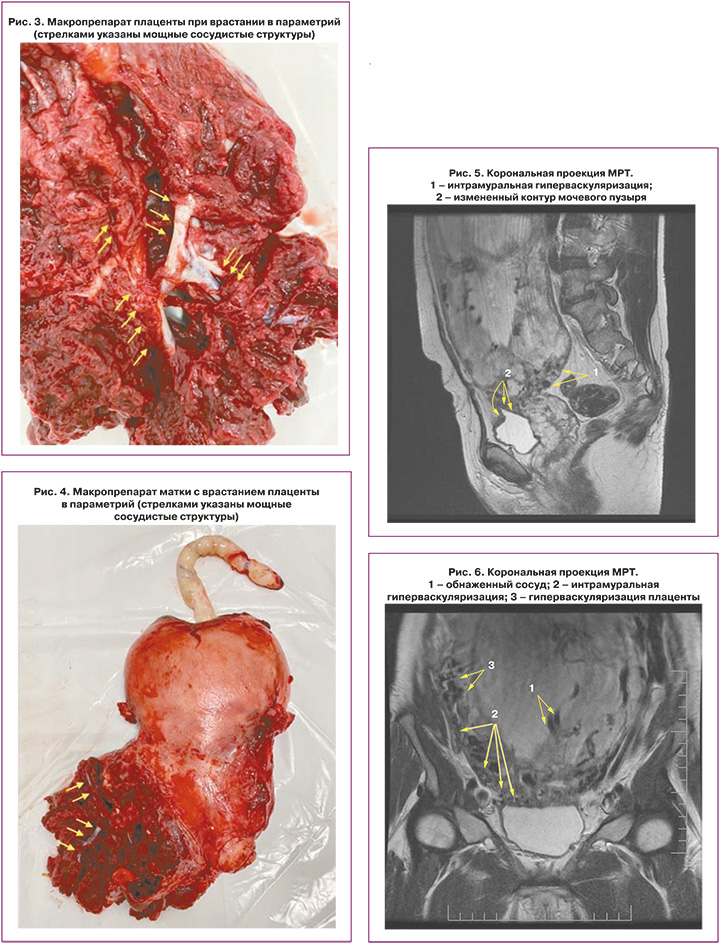

Является ли симптом «обнаженного сосуда» патогномоничным для параметральной инвазии или нет, еще предстоит выяснить; однако в ходе исследования установлена его связь с частотой гистерэктомий в группах с наличием симптома «обнаженного сосуда», что, вероятно, обусловлено мощной сосудистой сетью коллатералей и неоангиогенезом. Во всех случаях обнаружения данного признака впоследствии была выполнена вынужденная гистерэктомия (рис. 3–6, пациентка Н., 37 лет).

Также стоит выделить особый тип плацентарной гиперваскуляризации, а именно включение в плацентарной ткани изменений по типу «обнаженного сосуда» (рис. 1, 2). Мы провели анализ встречаемости данного признака среди наших пациентов. Любопытным наблюдением явилось то, что данный симптом в нашей выборке встречался только при наличии placenta percreta – 6 случаев, а именно при поражении параметриев, и не встречался при плацентарной инвазии, ограниченной миометрием. «Мостовидные сосуды» были менее специфичны, тем не менее, их наличие также сопровождало тяжелые формы врастания, обусловленные более глубокой инвазией ворсин хориона, – 8 случаев.

Дополнительный интерес в прогностическом плане вызывает симптом «обнаженного сосуда», представляющий собой хотя бы 1 линейную структуру диметром 5 мм и длиной около 2 см. Сама по себе гиперваскуляризация – признак при МРТ, имеющий специфичность до 80%; значения чувствительности колеблются от 42 до 69% [14]. При макроскопическом исследовании выявляется сеть субхорионических ветвистых стволовых сосудистых структур диаметром 3–5 мм, длиной 2–8 см [15]. Свое название они получили ввиду того, что минимально окружены тканями хориона и, проникая через толщу плаценты, давали минимальное количество ветвей. Dighe M. из Вашингтона опубликовала сходные данные о значимости диаметра внутриплацентарной сосудистой сети плода в прогнозе врастания плаценты; диаметр сосуда 2 мм или более часто встречался при наличии PAS, тогда как диаметр сосуда 3 мм или более был ассоциирован с более глубокой степенью инвазии и риском перипортальных кровотечений [16].